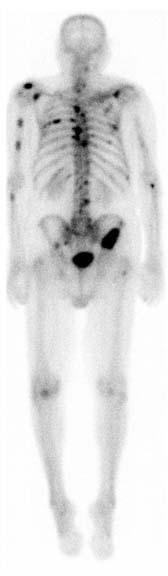

When it's time to do your scan, you'll be asked to lie on a table where a large camera called a scanner will measure how much of the radionuclide has been absorbed by your bones. You will be asked to move into different positions and hold very still so the camera can take pictures of all sides of your body. You may need to lie still for as long as 30 minutes. The radionuclide collects more in parts of the bone that are breaking down and repairing themselves, these show up darker on the scan and are called hot spots. A digital picture is made by the scanner which a radiologist or specialist uses to work out what's happening.

The amount of radionuclide that's absorbed depends on the amount of growth or activity in the bone.

• Test results are normal when the radionuclide is spread evenly throughout your body. This means that you're unlikely to have any major bone problems.

• Areas that absorb little or no amount of radionuclide appear as dark or "cold" spots. This could show a lack of blood supply to your bone, or certain types of cancer.

• Areas of bone growth absorb more radionuclide and show up as "hot" spots in the pictures. These may mean you have a problem (eg, cancer, a fracture or an infection).

Image credit: RadsWiki(external link) via Wikimedia Commons